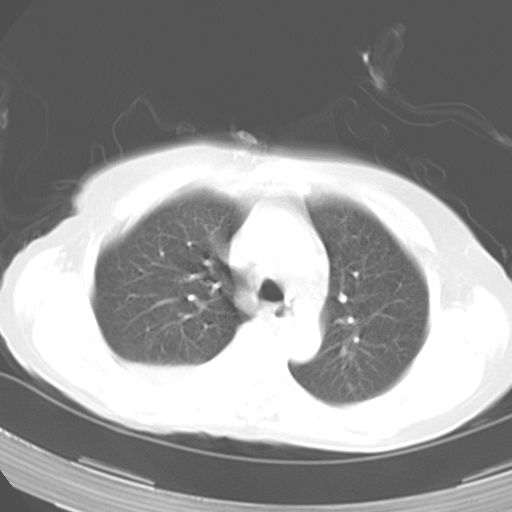

以下是引用dyqct在2006-12-7 21:08:00的发言:[br]考虑:1、肝内外胆管多发性结石伴肝左叶外侧段肝萎缩;[br] 2、右膈下多发脓肿;[br] 3、右侧少量胸腔积液、斜裂积液;[br] 4、左肾囊肿。

以下是引用jiazh在2006-12-7 20:37:00的发言:[br]肝脏周围半狐形低密度影,肝脏表面受压推移,考虑膈下脓肿可能性大;2、右侧胸腔积液

以下是引用拾荒者在2006-12-7 21:44:00的发言:[br]肝内外胆管多发结石,右膈下多发脓肿,右胸膜腔及叶间裂积液,左肾囊肿。[br] [br]